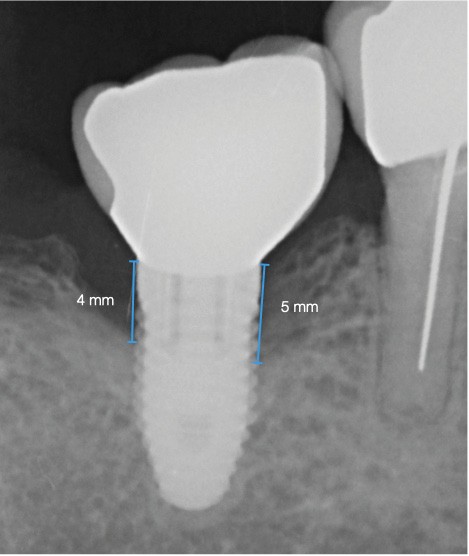

La patiente est restée 4 semaines sans couronne. Après l’intervention chirurgicale, elle a entamé un programme de soins péri-implantaires et parodontaux, avec des visites de rappel tous les 4 mois.

Dans les cas de traitement de péri-implantite, un suivi d’un an est considéré comme un suivi court. Néanmoins, le cas présent est stable après un an et ne présente aucun signe de récidive. Des contrôles supplémentaires sont nécessaires.